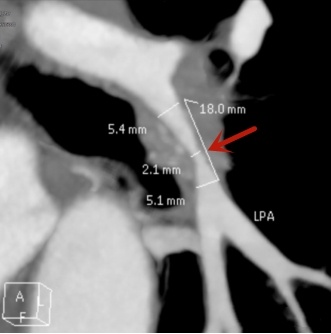

随后,史先生做肺血管增强CT检查,结果证实了医生们的猜测:他本该在纵隔腔内正常生长的左下肺动脉,却被增生的纤维组织包绕着,引发肺动脉狭窄。

史先生左下肺动脉被纤维组织增生包绕并出现狭窄。

原来,史先生两年前曾经左侧肋骨骨折,经过治疗后,骨折处愈合良好,但当时的外伤却导致纵隔内纤维组织增生,压迫到肺动脉,血液供氧不足,导致史先生反复胸闷、咳嗽。